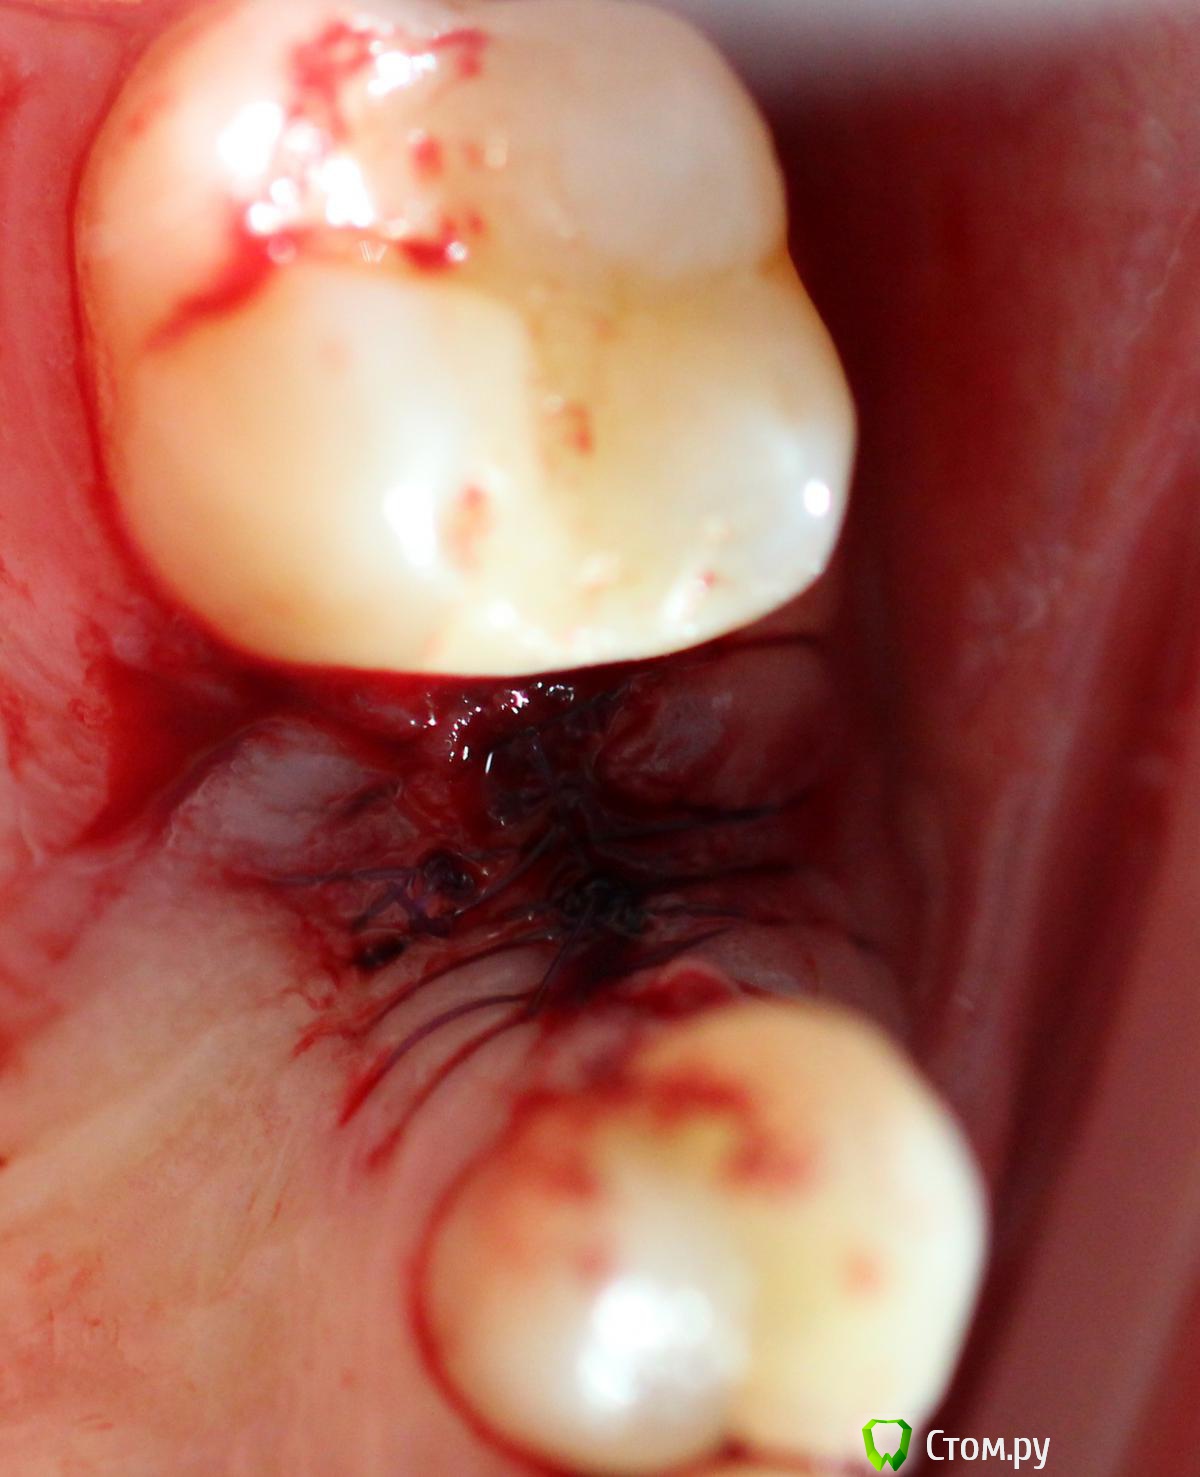

Andex Опубликовано 6 июля, 2014 Поделиться Опубликовано 6 июля, 2014 Всем привет! Вдохновленный великолепными кейсами докторов с форума, выкладываю свой случай. Коментарии и критика(особенно) приветствуются! Пациент обратился с переломом корня Я решил пойти по простому пути, тк мукогингивальными трансплантатами не владею в должном качестве - просто сошлифовал корень на 1,5 мм ниже прикрепления, и подождал 2 недели - знаю, что маловато, но руки чесались сделать операцию. Вид через 2 недели Удаляем корень и ставим имплант Устанавливаем заглушку Мобилизируем лоскут с неба и ушиваемся, нитка - моносин 5.0 Виновник торжества - слегка в стиле гиперреализма Снимки до и после имплантации - визиограф не информативен в полной мере - вживую имплант заглублен мах на 2 мм 4 Ссылка на комментарий